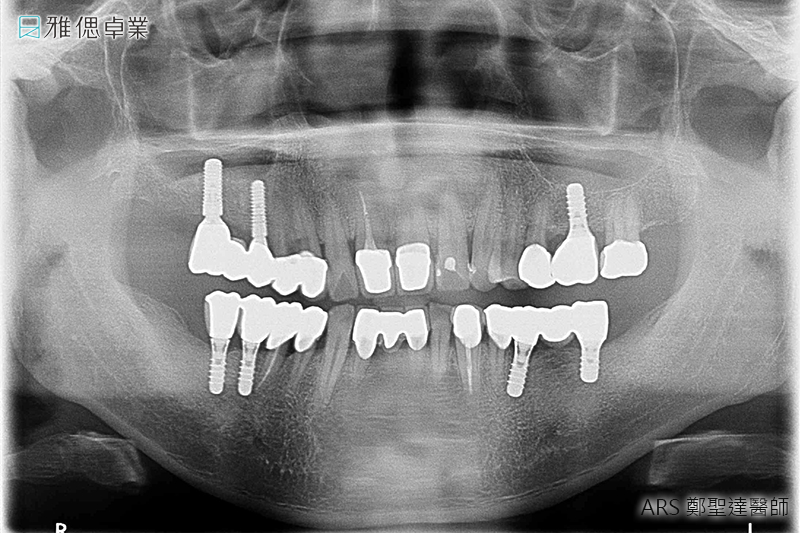

STEP4 取得牙套(假牙)主要模型

醫師會為您的植體設計客製化的支台齒(連結人工植牙與假牙),來支撐牙套,並且會為您和原本的牙齒進行比色,讓患者植牙完成時,假牙顏色不會和真牙顏色有所落差。

STEP6 正式牙套(正式假牙)完成

假牙會依據適合患者的咬合來做設計,若挑選全陶瓷假牙,它的高硬度及部分透光、美觀、咬合力量、高生物相容性、高密合度都會讓您照顧起來更加容易輕鬆。